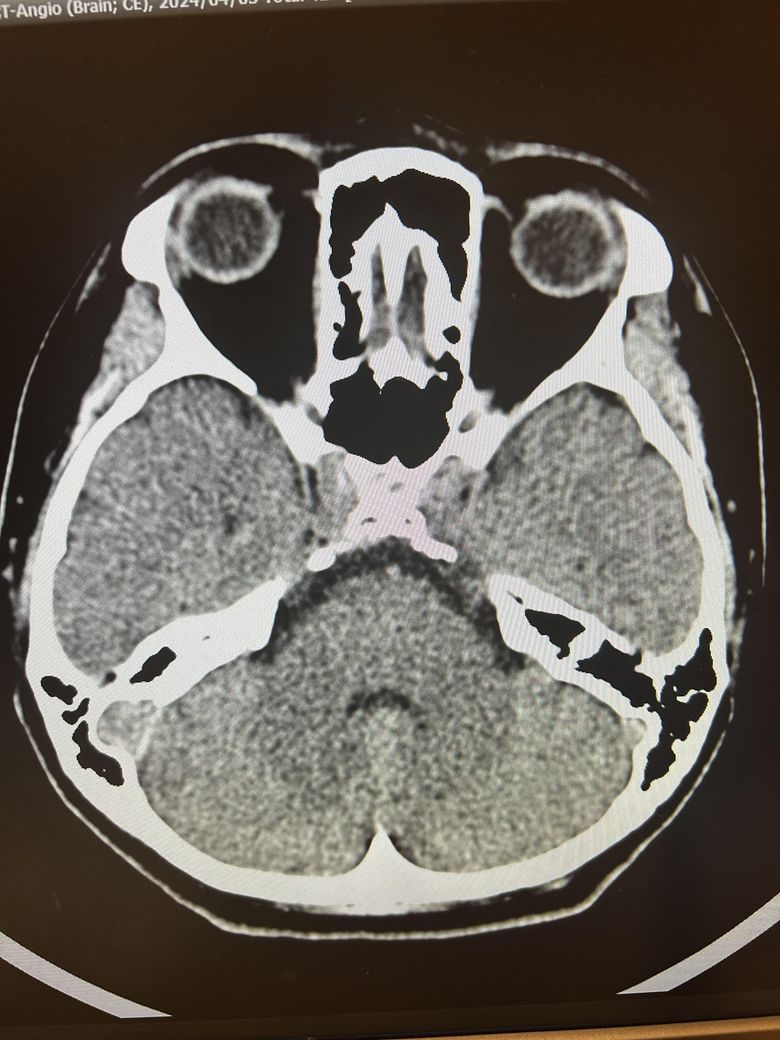

두통과 목뻐근함이 일주일째 심해서 뇌ct검사를 했습니다.

영상은 이렇게 보이는데 어떻게 의심되시나요?

석회화랑 다른것도 보이시나요?